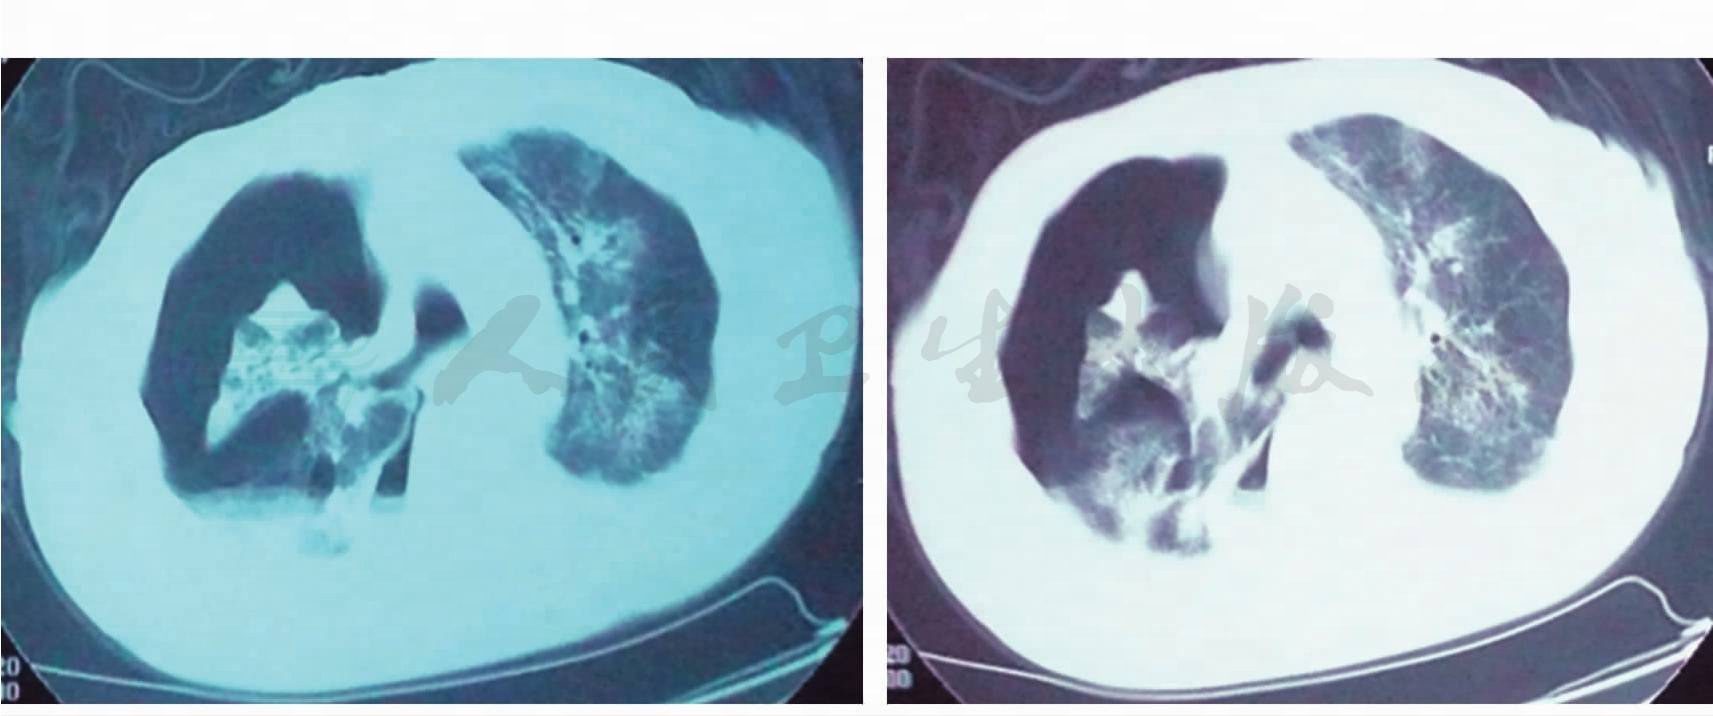

诊治经过:患者入院后查血细胞:WBC 4.0×109/L,N 79.1%。血浆Alb:27g/L。血气分析(呼吸空气):PaO2 79.1mmHg,PaCO2 41.2mmHg。考虑为社区获得性肺炎,所以给予左氧氟沙星抗感染治疗。在使用抗生素之前嘱患者清洁口腔后留取痰培养。体温一度正常。于入院后3天患者体温再次升高,达38℃,予对症处理。于入院第5天(左氧氟沙星应用第5天)(复查胸部CT回报:与2008年9月24日胸部CT比较,右肺下叶间质纹理较前增多,右中叶斑片条索影较前局限、浅淡,双肺胸膜下仍见多发磨玻璃影较前增多(图1,图2)。痰培养回报:大肠埃希菌(++++),ESBL(-),多种抗生素敏感。于是我们更换抗生素改为哌拉西林/他唑巴坦抗感染治疗。同日患者四肢、躯干出现红色斑丘疹,不痒,请皮肤科会诊考虑螨虫皮炎,未予特殊处理,数日后皮疹自行消退。入院第15天即哌拉西林/他唑巴坦治疗11天时,患者体温仍无下降趋势,再次复查血常规:WBC 7.97×109/L,N 95.7%。行纤维支气管镜检查并肺活检,镜下所见:大气道结节(图3)。于结节处取活检并行肺活检回报:①(大气道前壁)黏膜慢性炎症,被覆上皮磷化伴不典型增生,间质纤维组织增生;②(右肺下叶)黏膜慢性炎症,并见少许肺组织示间质纤维组织增生;③(刷片)未见肿瘤细胞。这时患者出现喘憋、呼吸困难,PaO2 56.3mmHg。再次复查胸部CT(2008年10 月23日)回报:①右肺膨胀不全伴右侧胸腔积气积液;②左上肺片状密度增高影,考虑感染(图4)。第2次痰培养回报仍为大肠埃希菌(++++),头孢哌酮/舒巴坦敏感,遂更换治疗。复查Alb 23g/L,静脉输注白蛋白纠正低蛋白血症。使用头孢哌酮/舒巴坦治疗5天,体温不见好转。为加强抗感染力度,换用亚胺培南/西司他汀治疗5天,临床症状仍不见好转。其间患者皮疹再次出现,且融合成片,请皮肤科会诊,建议皮肤活检,于肩背部皮肤活检组织回报:表皮内可见中性粒细胞脓肿,真皮浅中层血管周围弥漫炎症浸润,可见中性粒细胞、核尘。这时,我们考虑患者反复发热、抗感染治疗无效,是否同时存在非感染性疾病,于是查免疫全项:IgG 1130mg/ml↑,补体C3 1.3mg/ml↓,CRP 14.6mg/ml↑,类风湿因子1500U/ ml↑,角蛋白抗体(+),抗核抗体(-),抗中性粒细胞胞质抗体(-),请感染免疫科会诊考虑符合类风湿关节炎继发血管炎。于是加用甲泼尼龙40mg,静脉注射,每日一次治疗,2天后体温降至正常,用药7天后改为口服甲泼尼龙治疗,2周后复查胸部CT(2008年11月06日)右侧胸腔积气影消失,胸腔内积液明显减少,两肺上叶磨玻璃影消散(图5),于2008 年11月19日好转出院。住院期间治疗方案与体温变化见图6。

图4 (2008-10-23)右肺膨胀不全伴右侧胸腔积气积液,左上肺片状密度增高影

图5 右侧胸腔积气影消失,胸腔内积液明显减少,两上叶磨玻璃影消散